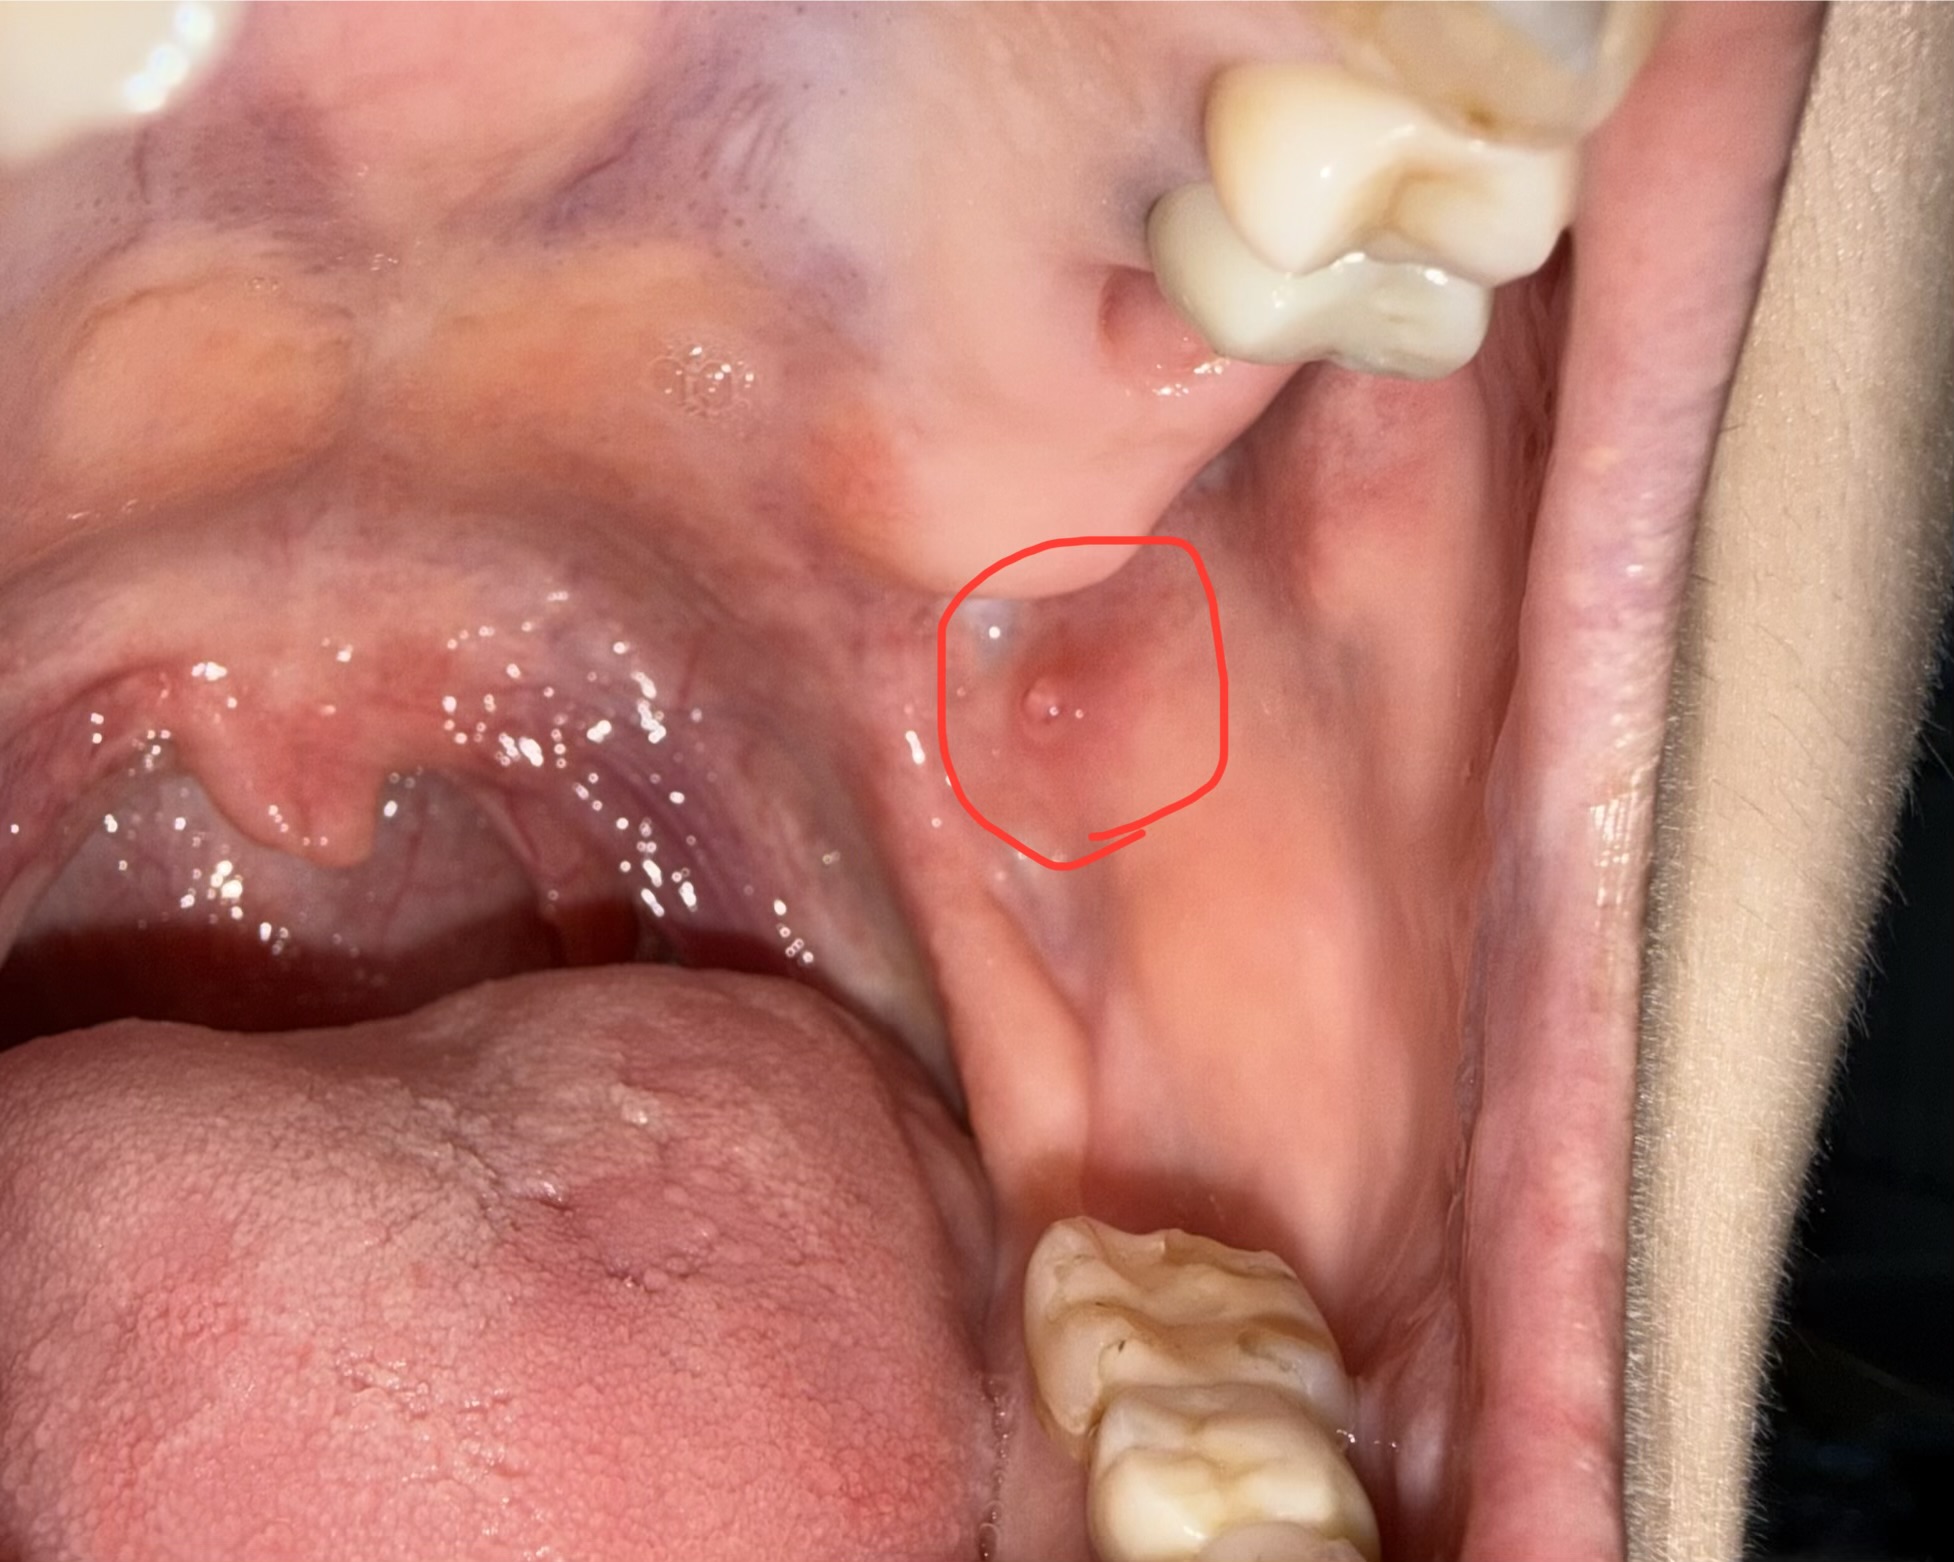

頬の内側に何度も血豆ができ治りません。食いしばりの影響でしょうか?

回答数:2 -